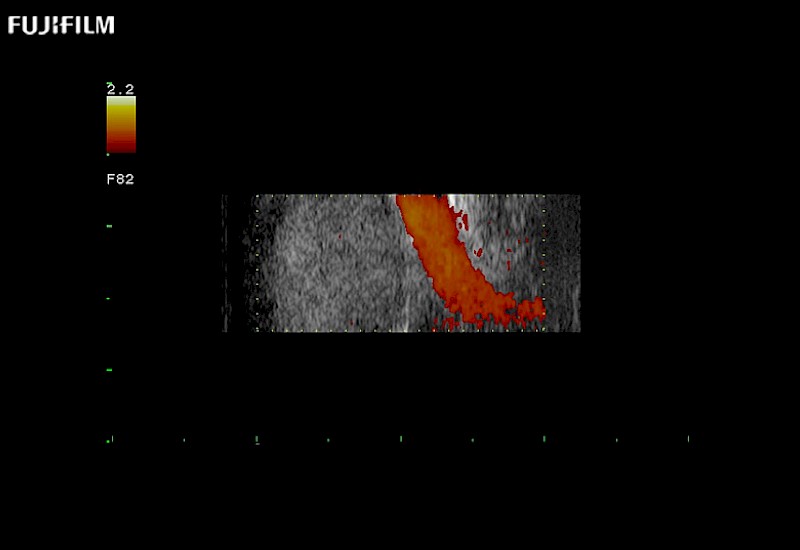

Exclusive 10mm side‐fire linear array transducer with 2.87mm diameter is ideal for real‐time visualization through and behind structures and instant, scalable definition of anatomy and vascularity including the ability to delineate and define tumor margins.

Guidance is the fundamental purpose for all of our surgical ultrasound technology. Fujifilm Healthcare is committed to designing tools that help neurosurgeons navigate inside the human body and provide the necessary information to immediately make critical surgical decisions.